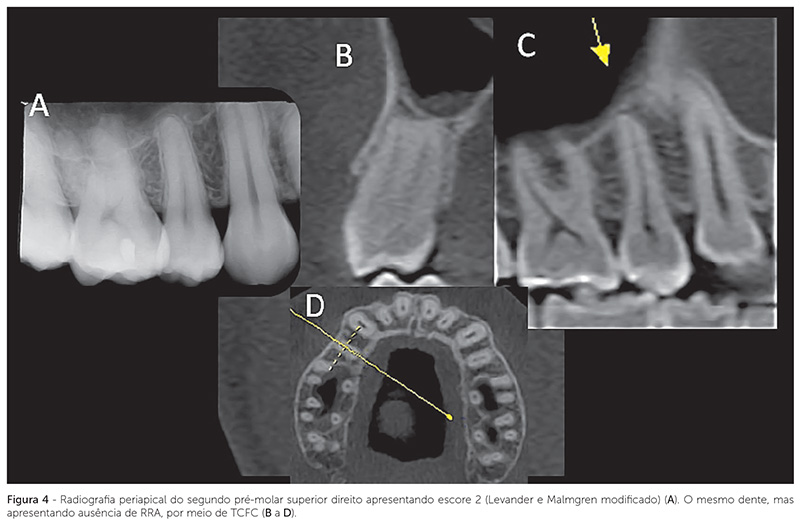

A Figura 2 mostra radiografias periapicais de um incisivo lateral maxilar, em que a RRA não alterou após a finalização do movimento ortodôntico em longo prazo. A Figura 3 mostra a diferença de detalhes de uma RRA em um incisivo central, por meio de TCFC e RP. A Figura 4 mostra a sobreposição de imagens, sugerindo RRA por meio de RP, enquanto a imagem de TCFC mostra ausência de RRA.

Evidenciou-se RRA em incisivo lateral superior sem alteração em longo prazo (Fig. 2); presença de RRA em incisivo central (Fig. 3) e ausência de RRA (Fig. 4) em pré-molar (superior), por meio de RP e de TCFC.

Esses resultados sugerem que as RPs, em função de limitações, tendem a superestimar as RRAs nos grupos dentários posteriores (Fig. 3, 4). Esses dados podem ser explicados em vista da presente análise ter sido para todos os grupos dentários. O grupo de dentes, as variações morfológicas apicais, a densidade do osso circundante (cortical óssea), a angulação dos raios, o contraste radiográfico e a sobreposição de estruturas anatômicas podem influenciar as interpretações radiográficas26. Na análise das imagens tomográficas, foi utilizada uma estratégia de navegação com intuito de verificar em todos os planos, o ápice das raízes, com recursos semelhantes aos sugeridos em recente estudo27. Essa estratégia favorece o perfeito manejo de imagens de TCFC, que podem revelar normalidades ou anormalidades incapazes de ser detectadas na RP convencional.